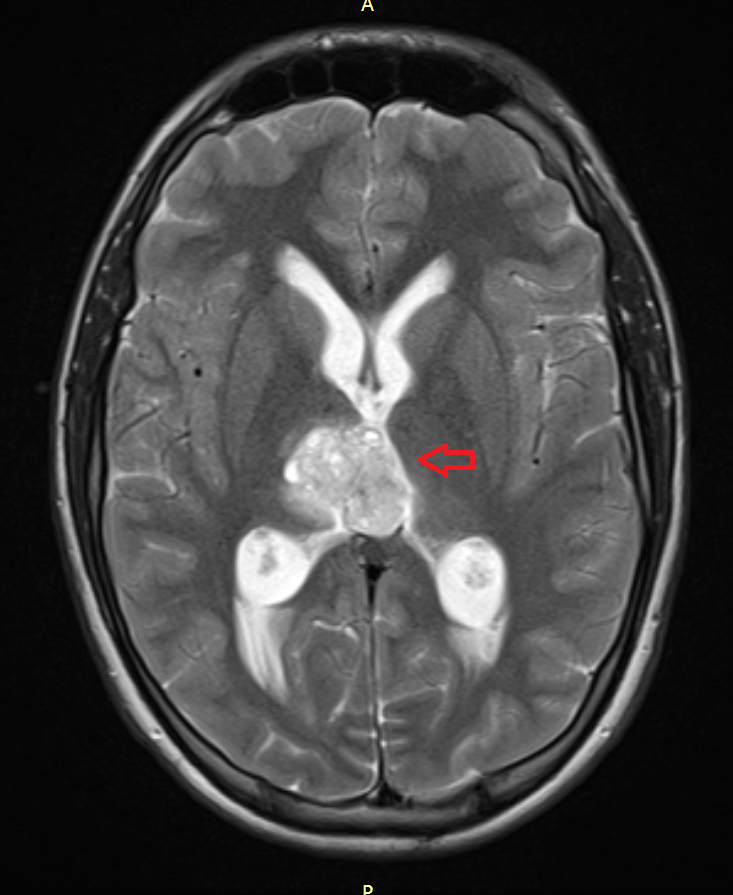

Головной мозг

Герминогенные новообразования в данной области – это примерно 2-4% от всех внутричерепных (интракраниальных). Патология в 75% случаев диагностируется у мальчиков, за исключением турецкого седла, где новообразования в основном локализуются у девочек.

Герминомы формируют инфильтрирующие опухоли больших размеров, часто являющиеся источниками субарахноидальных (между мягкой и паутинной оболочками мозга) и вентрикулярных (желудочковых) метастаз.

Risunok7.pngРисунок 7. – Герминома головного мозга.